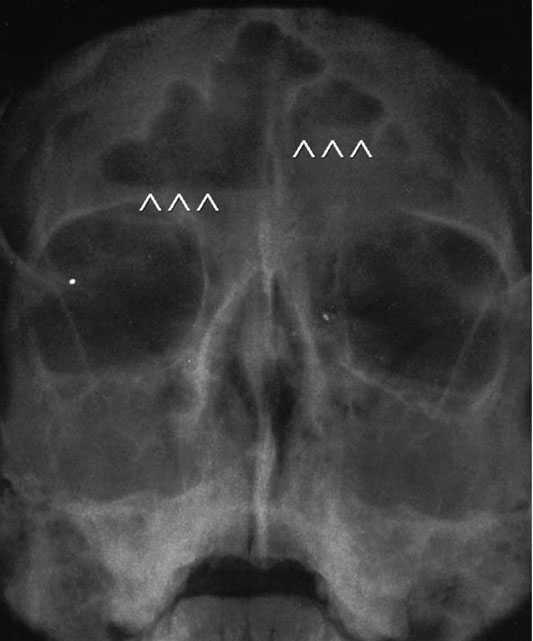

Los estudios radiográficos convencionales se indicarán atendiendo a los datos de la historia clínica. La radiografía de senos paranasales debe realizarse ante la sospecha de sinusitis (fig. 1). La radiografía craneal aporta escasa información en el estudio de las cefaleas (diastasis de suturas, fracturas, impresiones digitiformes).

Fig. 1. Sinusitis en un paciente de 13 años con cefalea frontal intensa. Ocupación predominante de senos maxilares y frontales (las flechas señalan la presencia de áreas de mucosa).